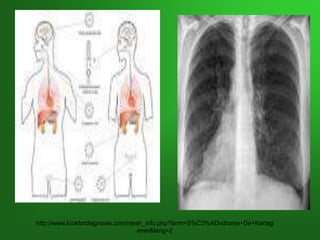

SÍNDROME DE KARTAGENER

Trastorno autosómico recesivo caracterizado por

DEXTROCARDIA, INFERTILIDAD Y SINUSITIS

Por mutaciones en los genes de DINEINA que

codifican proteínas de movilidad componentes de

las colas de los espermatozoides y de los cilios

respiratorios y tubáricos.

Llamada también:Discinesia Ciliar Primaria o

Tríada de Kartagener

http://www.lookfordiagnosis.com/mesh_info.php?term=S%C3%ADndrome+De+Kartag

ener&lang=2